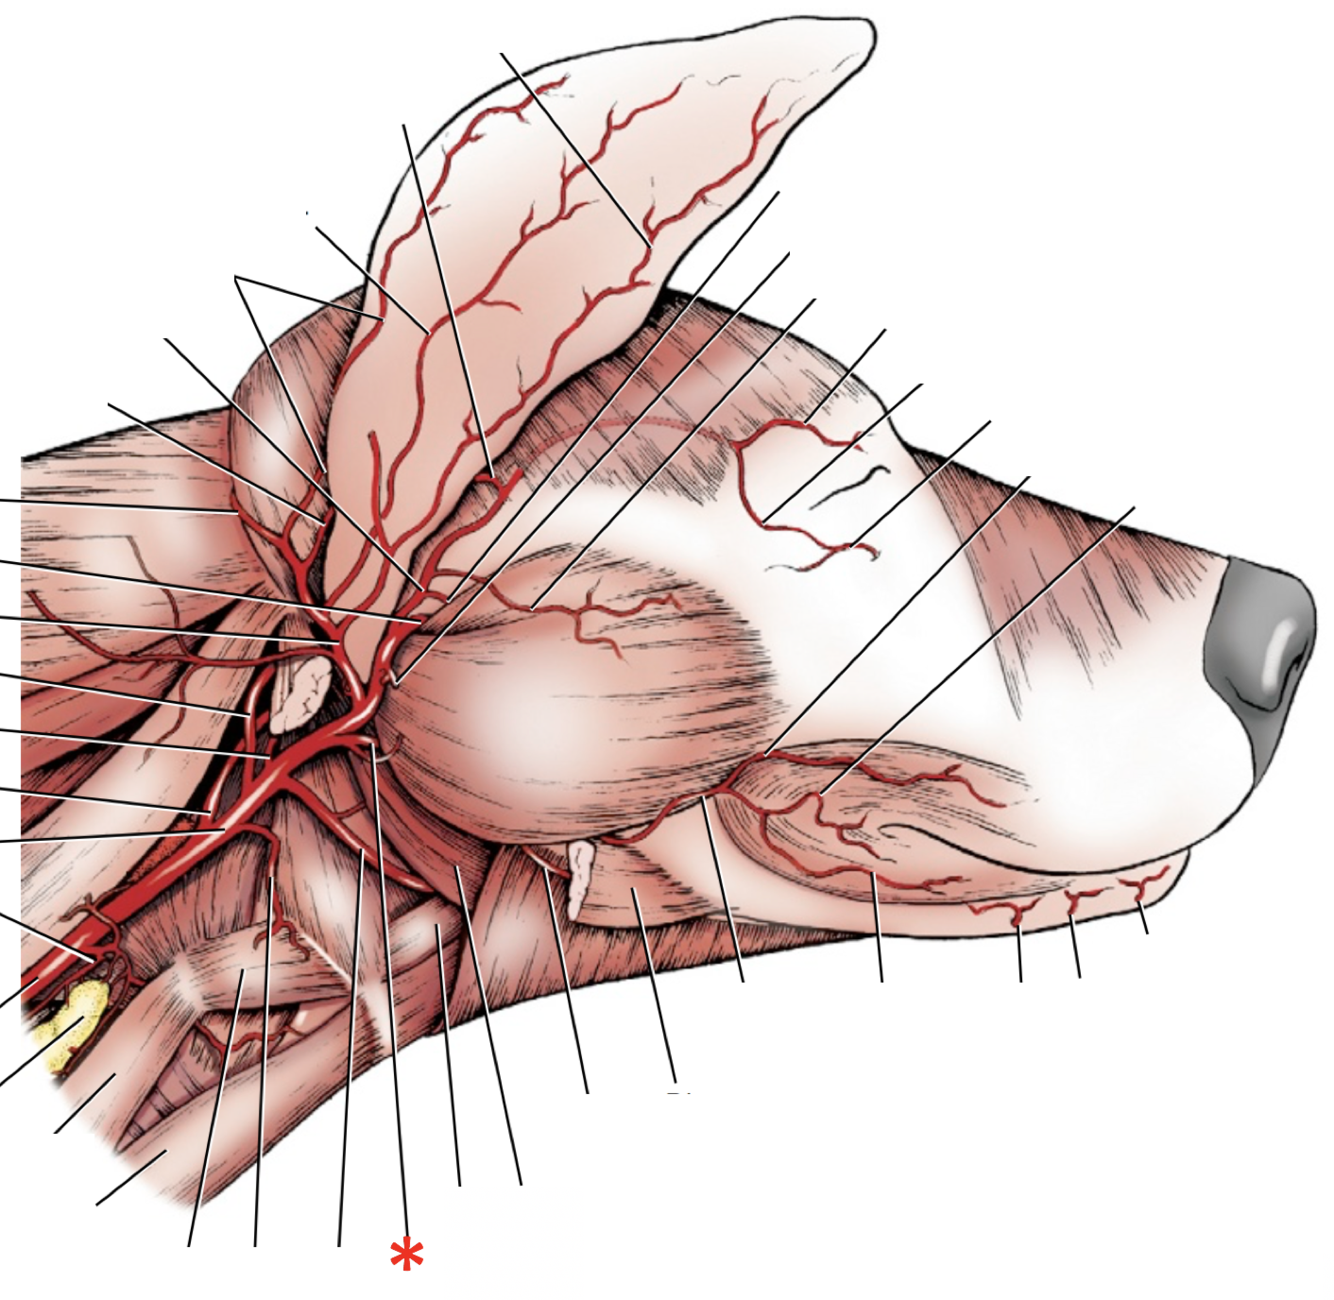

16

Q

6

A

A. occipitalis

17

Q

11

A

A. carotis externa

18

Q

12

A

A. laryngea cranialis

19

Q

13

A

A. lingualis

20

Q

14

A

A. facialis

21

Q

15

A

A. sublingualis

22

Q

19

A

A. auricularis caudalis

23

Q

21

A

A. temporalis superficialis

24

Q

24

A

A. maxillaris